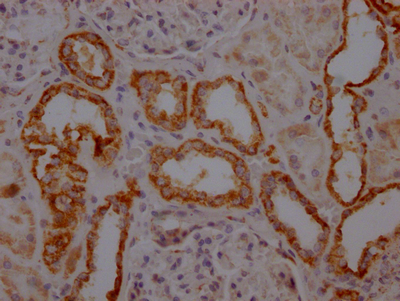

IHC image of CSB-RA277640A0HU diluted at 1:100 and staining in paraffin-embedded human kidney tissue performed on a Leica BondTM system. After dewaxing and hydration, antigen retrieval was mediated by high pressure in a citrate buffer (pH 6.0). Section was blocked with 10% normal goat serum 30min at RT. Then primary antibody (1% BSA) was incubated at 4℃ overnight. The primary is detected by a Goat anti-rabbit IgG polymer labeled by HRP and visualized using 0.05% DAB.